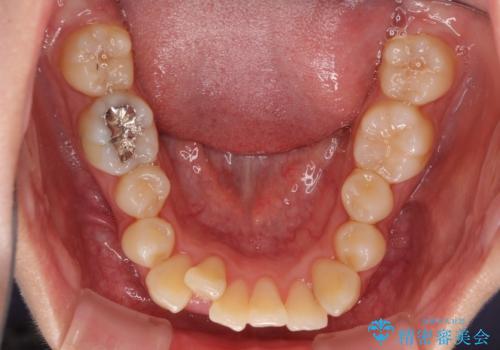

- 上下のデコボコと前歯のクロスバイトを改善したいとのことで来院された患者様です。

極力短期間で治療したいとのことで、ワイヤー装置による矯正治療を行うこととしました。